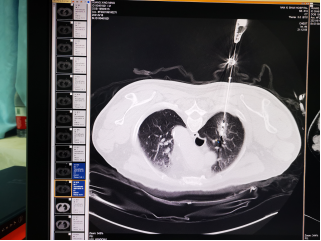

肺结节是指肺部组织出现的结节性病变,属于肺部的占位病变,是一种肉芽肿性疾病,通常直径小于3厘米都称之为肺结节。肺结节一般表现为类圆形、不规则性病灶。是一种临床常见的病症。

微波消融是目前治疗肺结节的首选治疗方法。微波消融属于热性的消融方法,是在肺结节的局部形成高温,使组成肺结节的细胞,在高温作用下出现变性、坏死,达到完全治疗的作用。微波消融损伤比手术损伤小,比微创手术还要小。